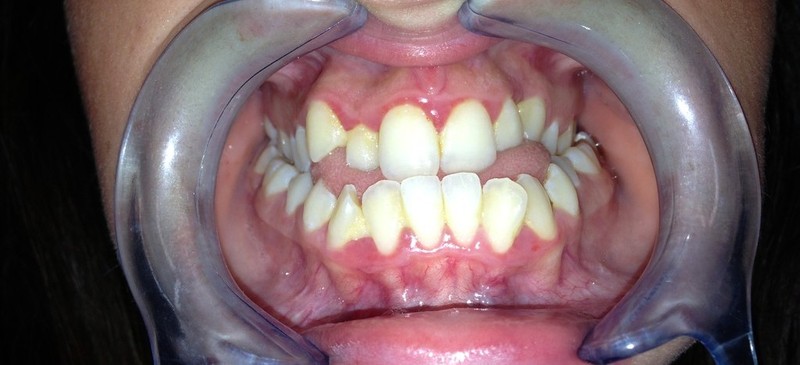

I risultati Arrivano e si vedono.

Uno dei nostri ultimi cambiamenti radicali.Il tuo sorriso può essere più vicino di quello che immagini

Total Dental MakeOver presso lo studio di implantologia sicilia del dott Gabriele Mirabella.